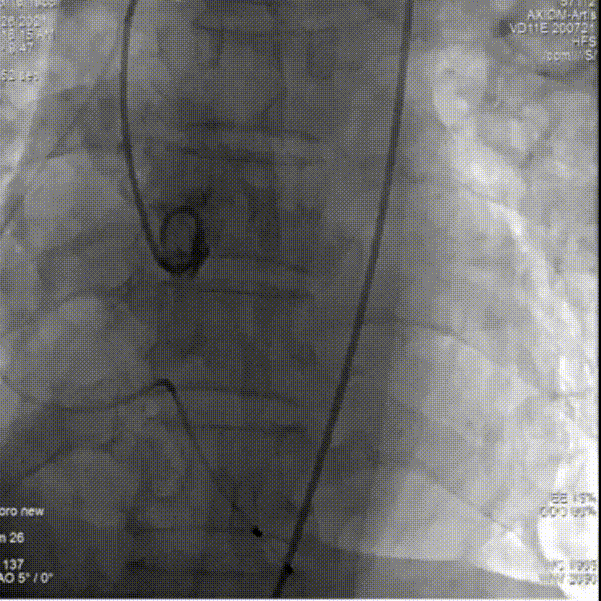

人工瓣有相应折叠,全部回收撤出体外

更换后瓣膜再一次进行释放

部分回收进行位置的微调整

完全释放后,主动脉根部造影